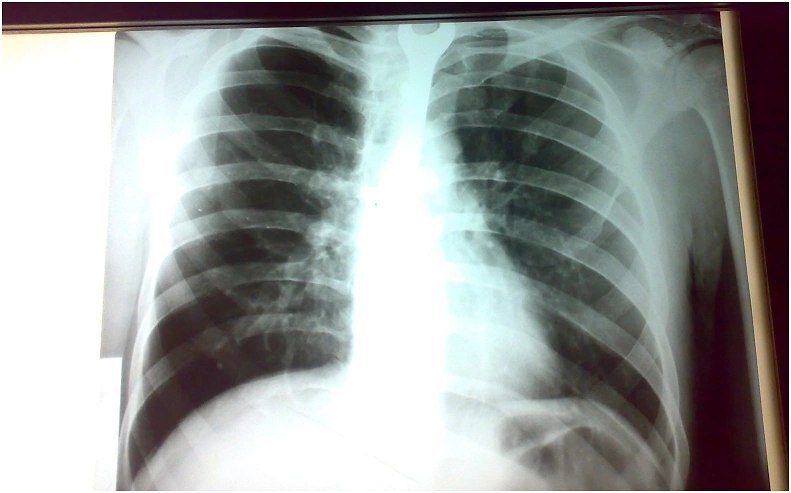

Гемодинамически пациент был стабилен. Артериальное давление составляло 130/80 мм рт. ст., частота пульса - 88 ударов в минуту. Он был направлен на рентген грудной клетки, который показал аномальный рентгеноконтрастный инородный объект внутри пищевода и тень в середине рентгенограммы грудной клетки, часть которой была стерта сердцем и тенью позвонка Фото 1.